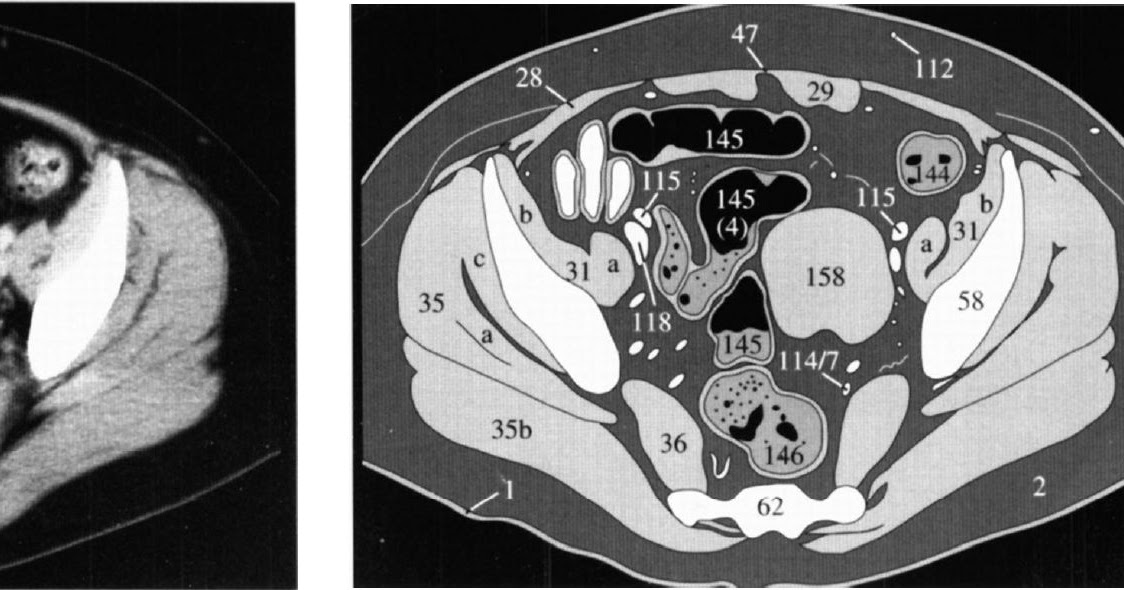

Мрт брюшной полости и забрюшинного пространства подразумевает сканирование печени и гепатобилиарного тракта, селезенки, поджелудочной железы, видимых лимфатических узлов, почек и надпочечников.

МРТ брюшной полости и таза проводится для выявления проблем, связанных с:

- Печень

- Почки

- Селезенка

- Кишечник

- Поджелудочная железа

- Надпочечники

- Органы малого таза